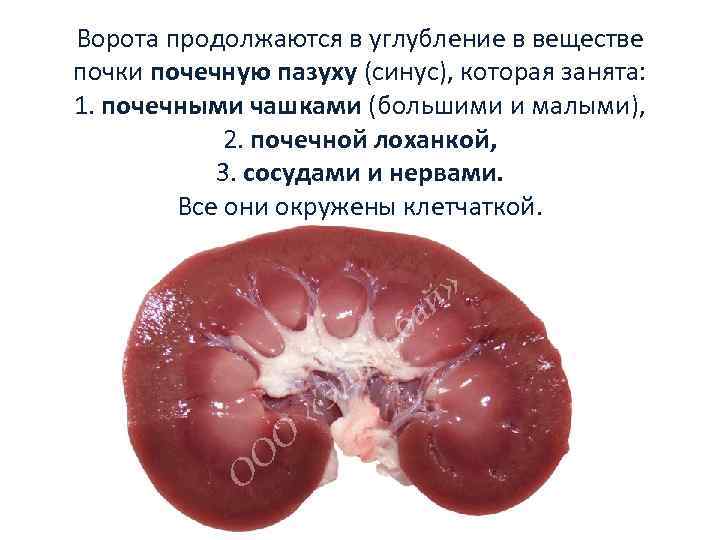

Ворота продолжаются в углубление в веществе почки почечную пазуху (синус), которая занята: 1. почечными чашками (большими и малыми), 2. почечной лоханкой, 3. сосудами и нервами. Все они окружены клетчаткой.

Ворота продолжаются в углубление в веществе почки почечную пазуху (синус), которая занята: 1. почечными чашками (большими и малыми), 2. почечной лоханкой, 3. сосудами и нервами. Все они окружены клетчаткой.